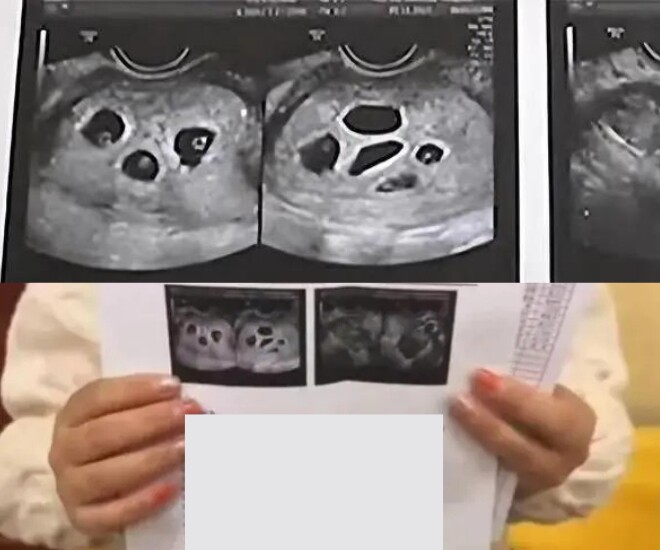

Vào một buổi sáng năm 2021, cô Bạch năm đó 18 tuổi, đã kết hôn được 2 năm thì phát hiện cơ thể có dấu hiệu bất thường nên đã cùng mẹ chồng đến bệnh viện địa phương để kiểm tra sức khỏe. Sau khi tiến hành siêu âm, gương mặt bác sĩ bỗng trở nên căng thẳng. Cuối cùng, bác sĩ thông báo cô đang mang thai 6 bé. Cả cô và mẹ chồng không dám tin vào tai mình, liên tục hỏi lại để chắc chắn. Dù bác sĩ xác nhận kết quả, họ vẫn được khuyên nên đến một bệnh viện sản lớn hơn để kiểm tra lại. "Để chính xác hơn, bạn nên đến một bệnh viện lớn khác để khám lần nữa”, bác sĩ nói.

Ngay sau đó, hai người tới Bệnh viện Phụ sản Trịnh Châu. Tại đây, kết quả siêu âm tiếp theo còn gây choáng váng hơn, cô Bạch được kết luận đang mang thai 8 bé, tăng 2 bé so với lần khám đầu tiên. Cả ê-kíp y bác sĩ lẫn người nhà đều không khỏi sững sờ trước kết quả hiếm thấy này. Bác sĩ cho biết việc mang 8 thai là một điều kỳ tích về mặt y học, với xác suất xảy ra cực kỳ thấp, bởi điều đó đồng nghĩa với việc cơ thể đã rụng nhiều trứng trong một chu kỳ và tất cả đều được thụ tinh thành công.